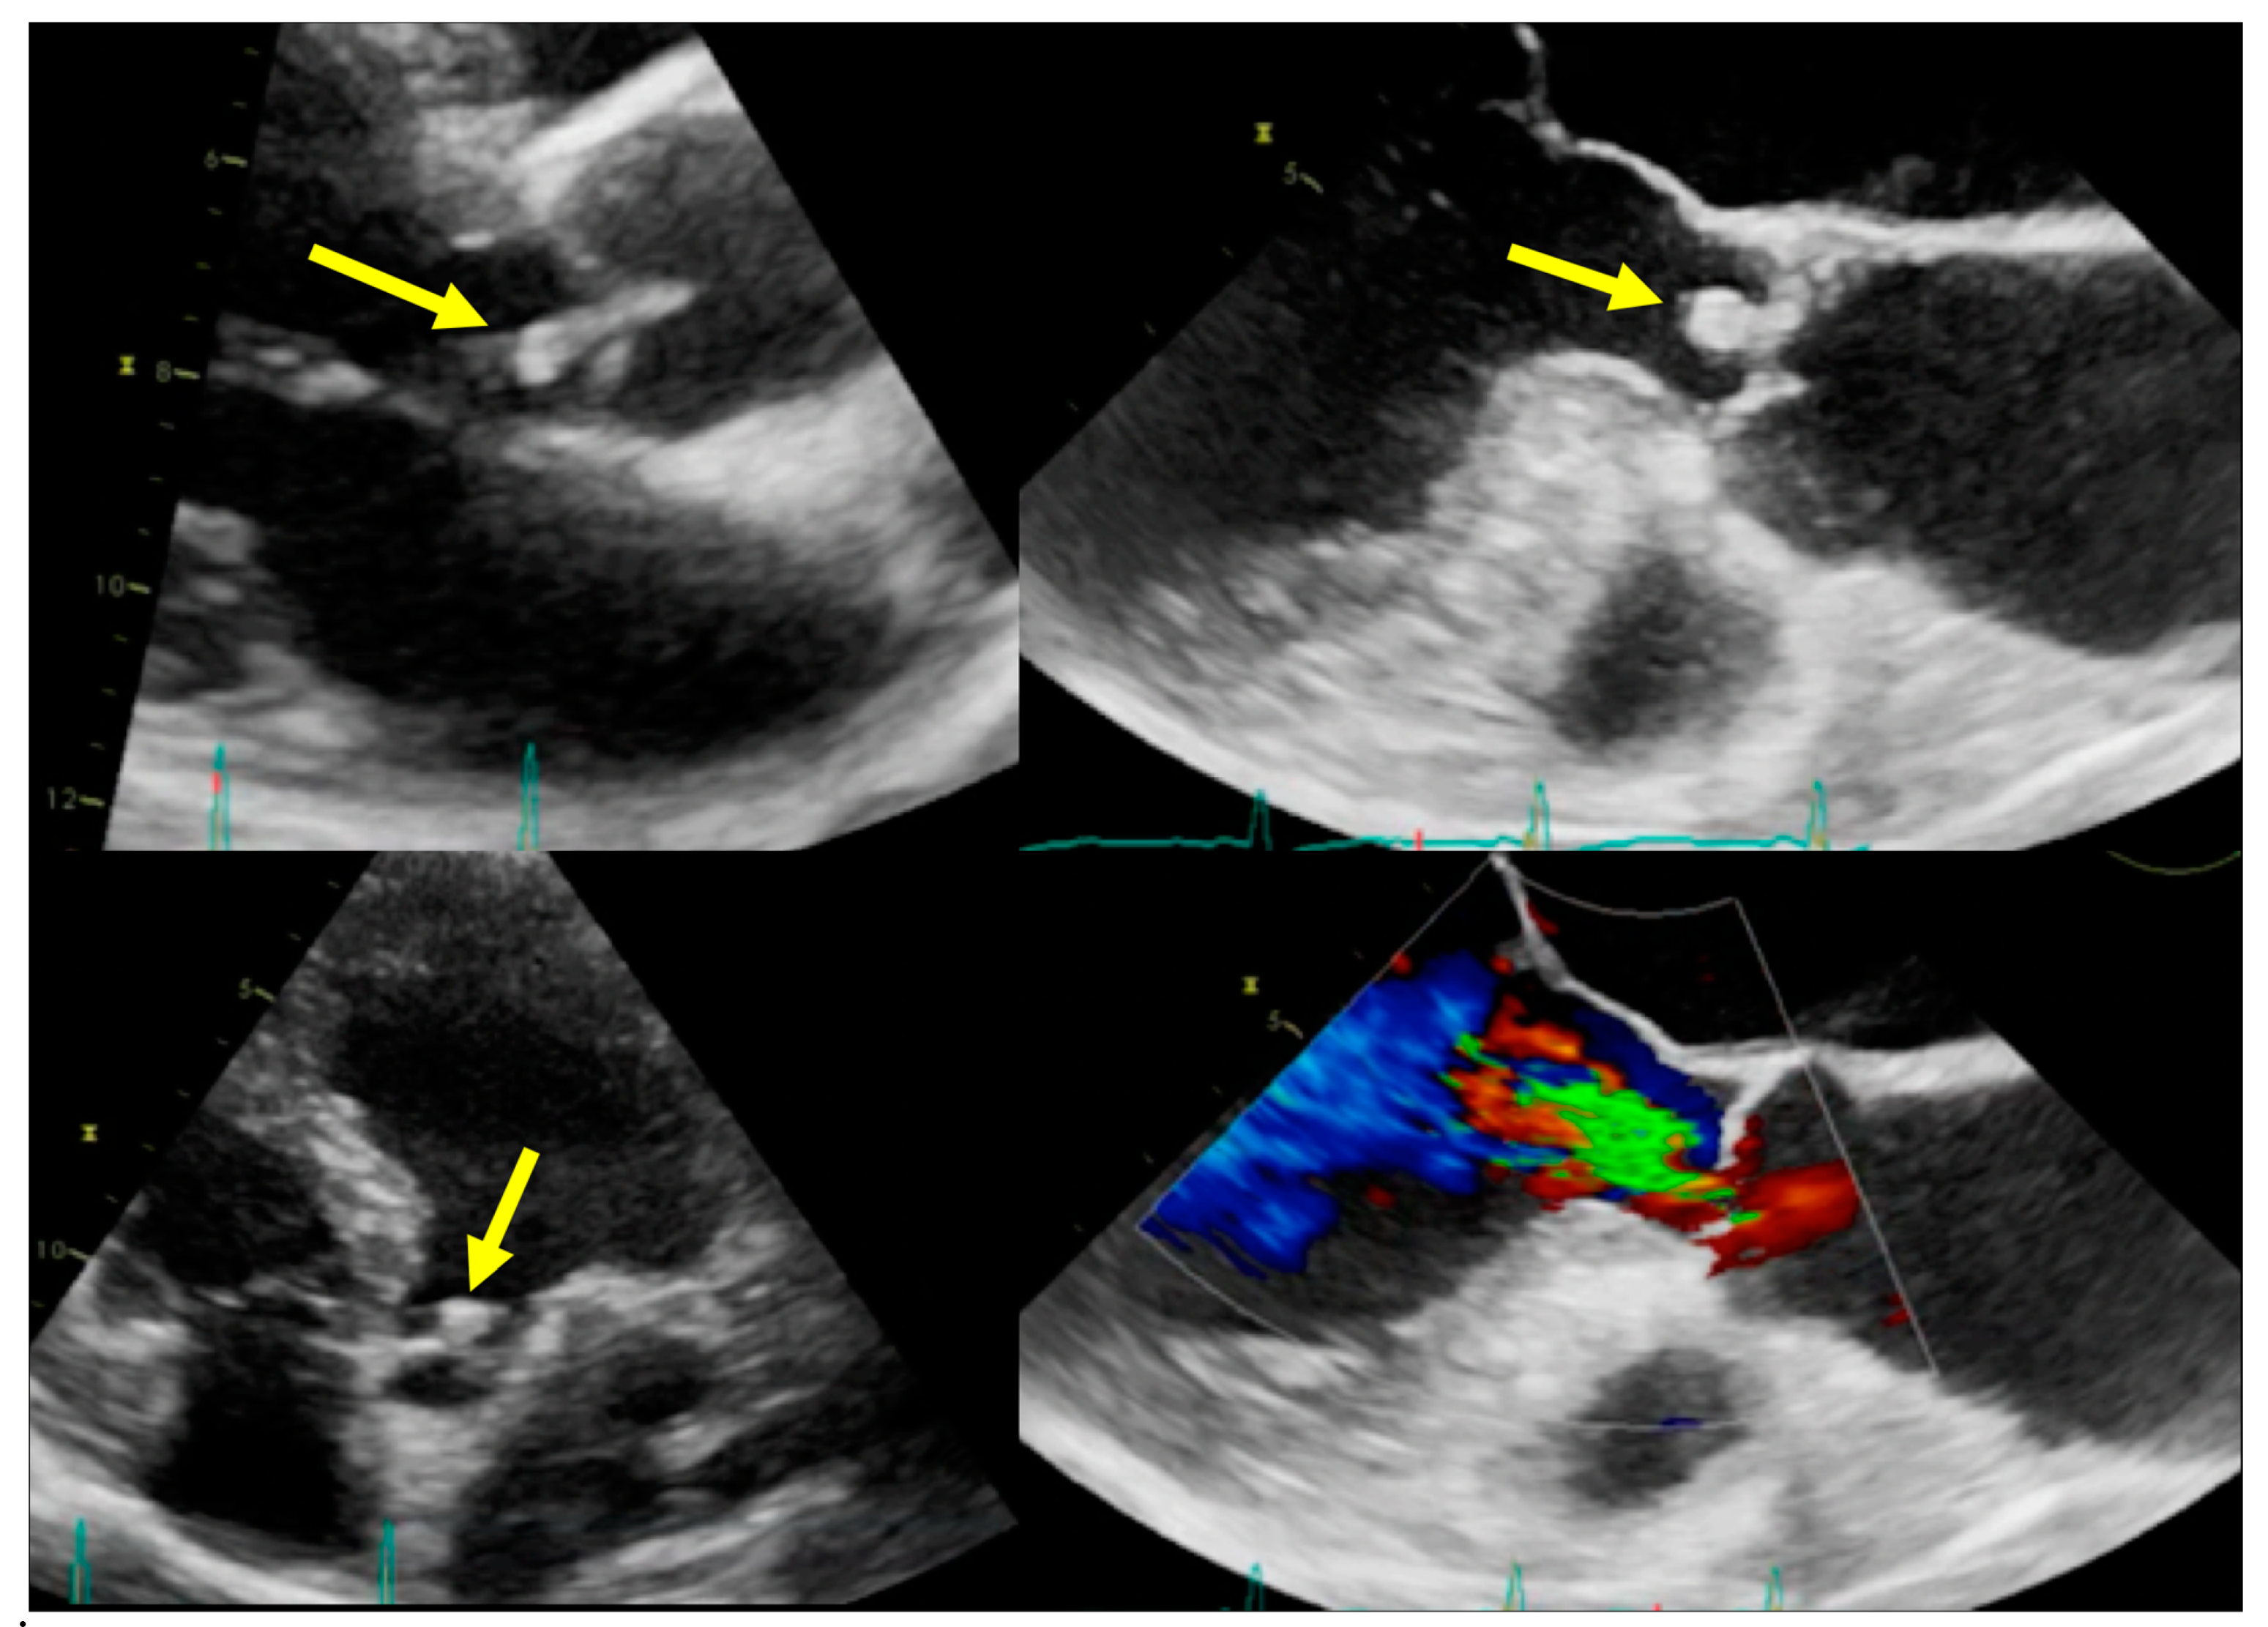

4.2. When to Ask for Transthoracic Echocardiography (TTE) and When to Ask for Transoesophageal Echocardiography (TOE)

5.2. When to Ask for TTE and When to Ask for TOE

| Left-sided IE | Good visualization of mitral and aortic valve. Valvular dysfuction assessment. Identification of complication (i.e., valvular regurgitation). | Difficult differential diagnosis in presence of marantic vegetations or high calcification. | Detection of vegetations and valve perforation. Assessment of perivalvular extent of disease (abscesses, pseudoaneursysm, fistula). | Inferior to TTE/TOE in detecting small vegetations (<2 mm). | Prognostic assessment: simultaneous detection of embolism, metastatic lesions and portal of entry. | Limited sensitivity for small vegetations. | Evaluation of distant emboli and portal of entry. | Limited role because of low sensitivity for small vegetations. | Capability to assess vegetations (inferior to TTE/TOE). Capability to assess local complications. Independent by acoustic window. May detect concomitant myocardial inflammation. | Not included in current guidelines for IE diagnosis. |

| Right-sided IE | TTE generally provides good visualization of tricuspid valve. TOE is useful in the assessment of IE related to CHD. | Pulmonary valve is difficult to assess. | ||||||||